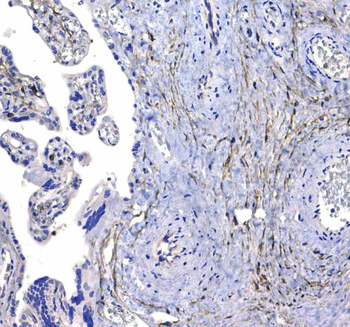

10 μg, 100 μg - Anti-HSD11B2 Antibody [orb316541]

IF, IHC, IHC-Fr, WB

Human, Mouse, Rat

Rabbit

Polyclonal

Unconjugated

10 μg, 100 μg - Anti-CD44 Antibody [orb402179]